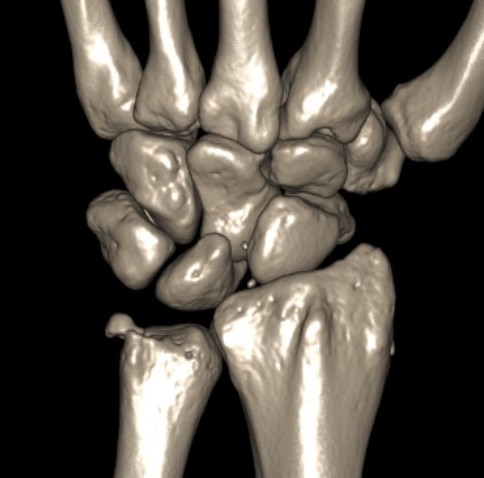

Isolated dorsal dislocation DRUJ

Isolated dorsal DRUJ instability with ulna sided TFCC tear

CT

Dorsal subluxation of the distal ulna

MRI demonstrating dorsal distal ulna subluxation associated with significant ligament disruption